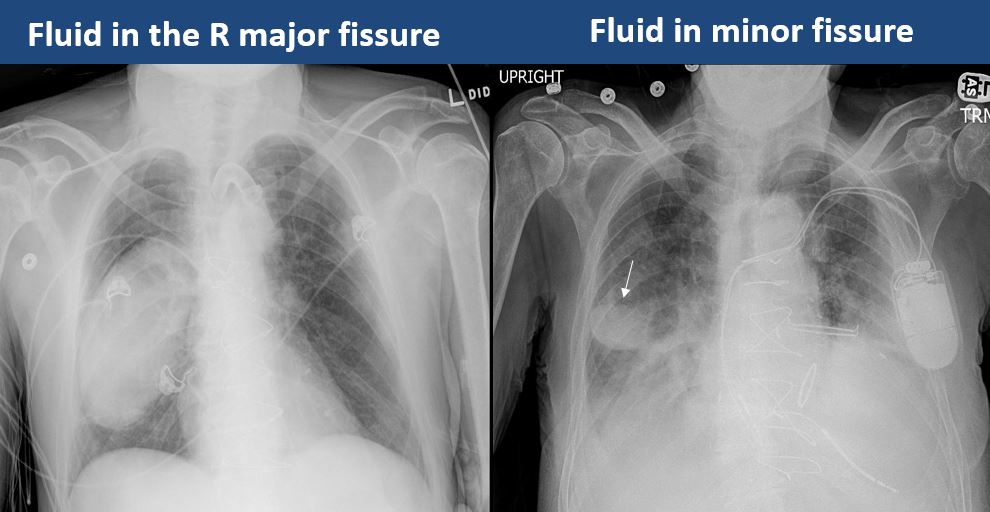

There is a pleural effusion or blunting of the costophrenic angle. |

Yes | NA |

There is focal fluid in the fissures. |